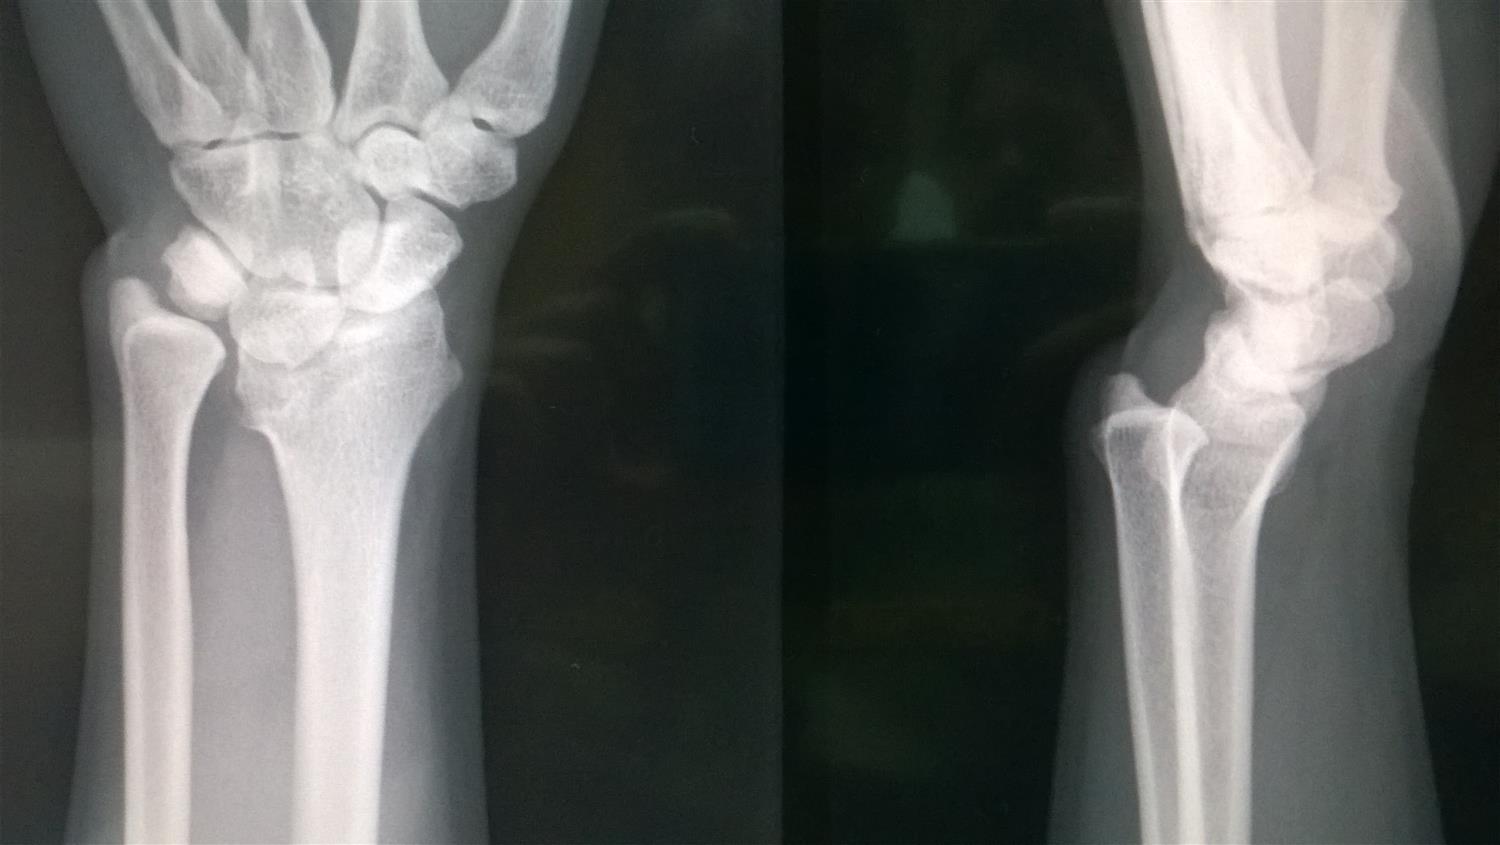

Madelung's Deformity Hand Orthobullets Gun Stock Deformity Orthobullets Typically, malunion of supracondylar fractures often leads to cubitus varus, or gunstock deformity. this condition is a triplanar. On exam, her arm is held in 30 degrees of extension and she is unable to move her elbow due to pain. Typically, malunion of supracondylar fractures often leads to cubitus varus, or gunstock. 1 although simply termed “cubitus varus,” the deformity. Gun Stock Deformity Orthobullets.